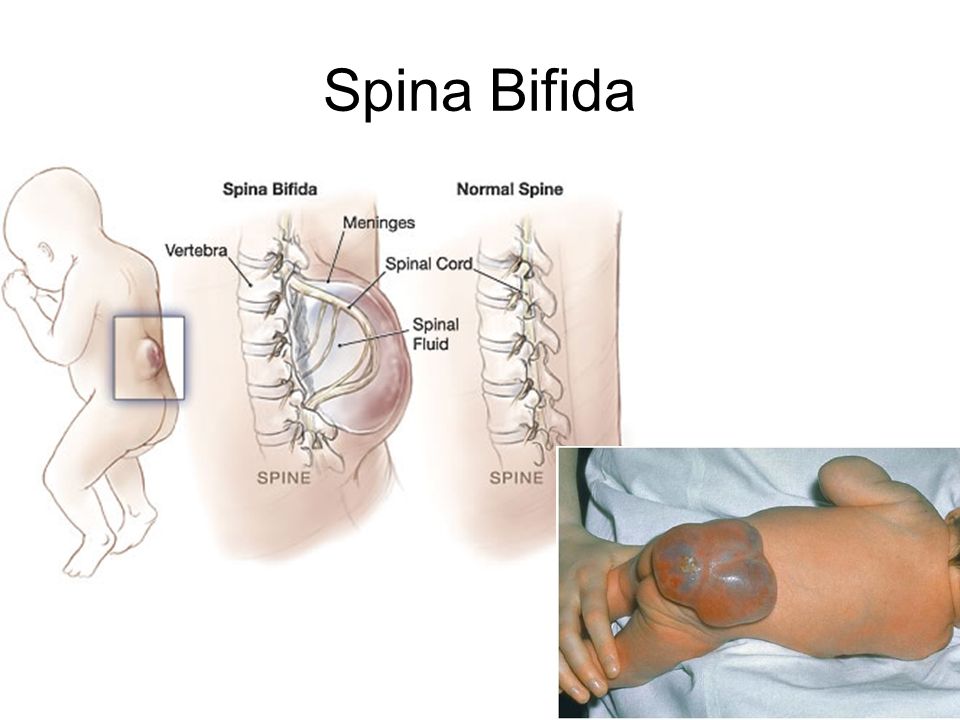

Рентген шейных позвонков при спина бифида

Раздел: Фотозарисовки